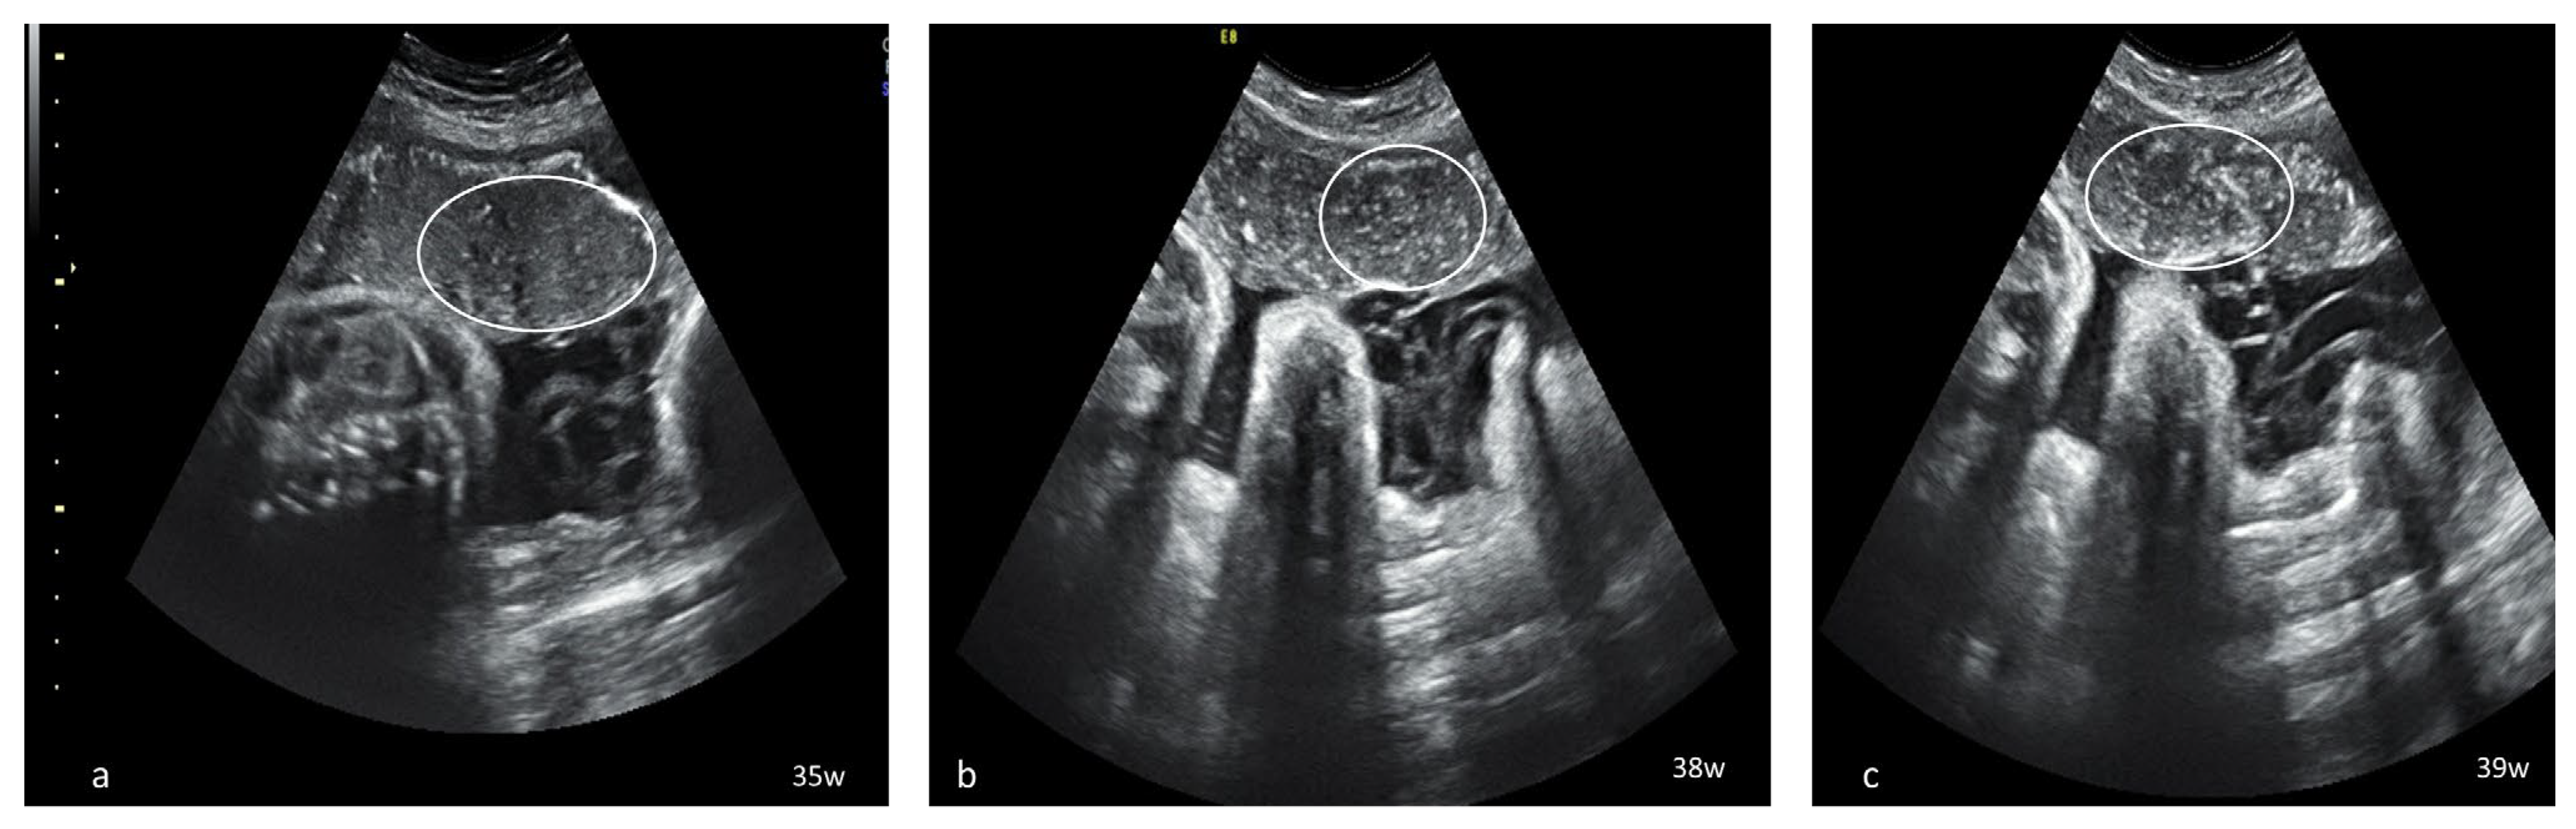

Dynamic evaluation of the placental morphology revealed what seems to be a particular pattern of placental remodeling starting from 30 WG towards term following SARS-CoV-2 infection during pregnancy. We noted the occurrence of dispersed hyperechoic foci, without posterior acoustic shadowing, scattered across the placenta, increasing in number and size with consecutive examinations, creating a “starry sky” appearance similar to the sonographic pattern described in acute hepatitis (Figure 1) [22]. Consequently, these foci conflate to form interlobular, chandelier-like, comma-shaped indentations. Later, lesions organize to form a consistent, chalky conglomerate along the entire basal plate, a “white line”, with bolded edges towards the chorionic plate forming white angles (Figure 2). Placental changes mimic the physiologic aging process but occur earlier in gestation; echo-dense foci are more widespread and organize in a short period to form the echoic white line.

Figure 2.

Serial placental ultrasound images at 31 WG, 36 WG and 38 WG, respectively, of a nullipara with confirmed SARS-CoV-2 infection at 24 WG (a) the “white line” (arrow) beginning to form at the level of the basal plate; (b,c) continuous “white line” with bolded angles towards placental margins.